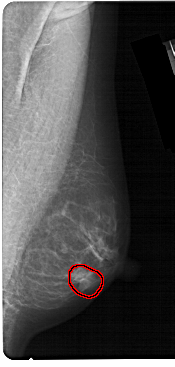

A_1304_1.RIGHT_CC

FILE: A_1304_1.RIGHT_CC.OVERLAY

TOTAL_ABNORMALITIES 1

ABNORMALITY 1

LESION_TYPE MASS SHAPE OVAL MARGINS CIRCUMSCRIBED

ASSESSMENT 4

SUBTLETY 4

PATHOLOGY BENIGN

TOTAL_OUTLINES 1

BOUNDARY